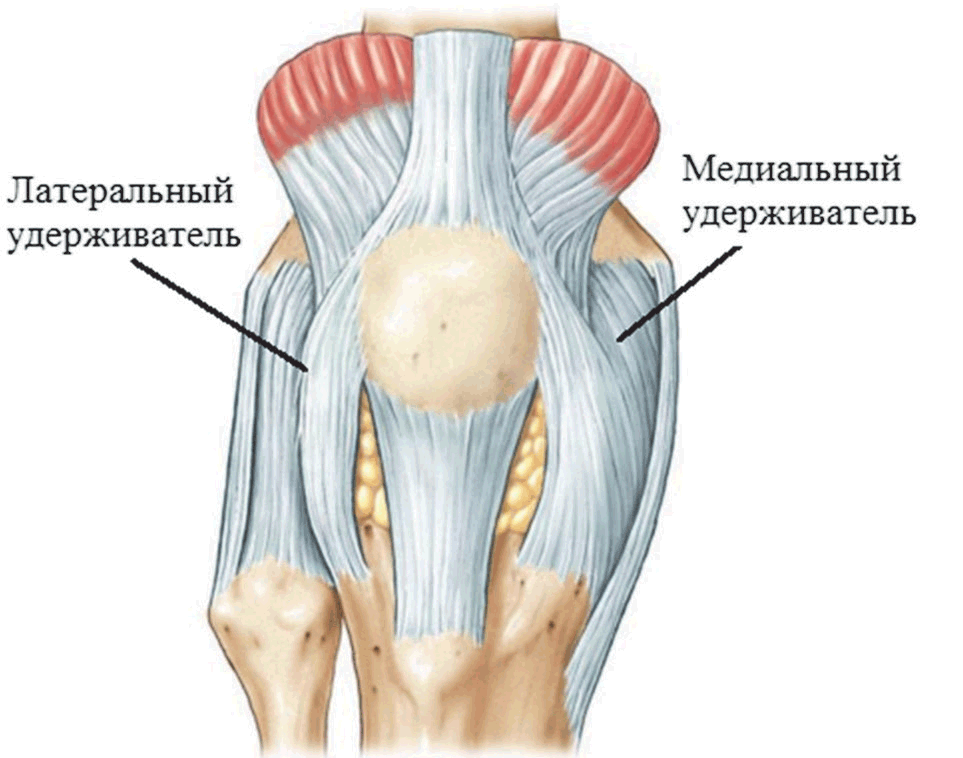

Супрапателлярный импиджмент коленного сустава: симптомы и лечение